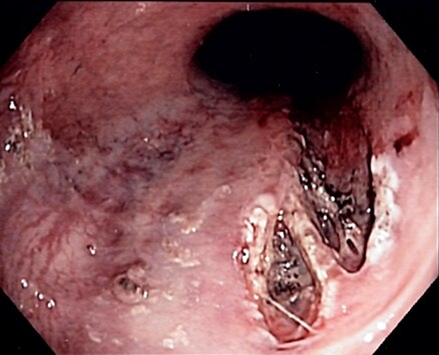

Эндоскопическая картина СМВ:

Комментарии: эндоскопическое исследование подтверждает наличие разрыва стенки пищевода и/или желудка, уточняет его локализацию, форму, размеры, глубину, наличие грыжи пищеводного отверстия диафрагмы и рефклюкс-эзофагита.

Комментарии: в таких случаях важным является обеспечение адекватной медикаментозной профилактики рецидива кровотечения. Эндоскопическую остановку (профилактику рецидива) кровотечения необходимо выполнить в течение 2 часов от момента госпитализации пациента. У пациентов с СМВ для эндоскопической остановки кровотечения из разрывов и профилактики его рецидива целесообразно применять инъекционный метод гемостаза в сочетании с термическими (диатермокоагуляция, аргоноплазменная коагуляция (A22.30.033.001)) или клипирование (Остановка кровотечения из периферического сосуда; Остановка кровотечения из периферического сосуда эндоскопическая с использованием электрокоагуляции; Остановка кровотечения эндоскопическая с использованием термокоагуляции, Клипирование кровоточащего сосуда эндоскопическое, Коагуляция кровоточащего сосуда аргонплазменная) [13,14,19,23]. Инъекционный гемостаз в качестве монотерапии не обеспечивает должной эффективности и должен применяться только в комбинации с другими методами эндоскопического гемостаза. Как дополнение к комбинированному эндоскопическому гемостазу могут быть использованы и другие местные методы эндоскопического гемостаза [13,14,19,23,31].